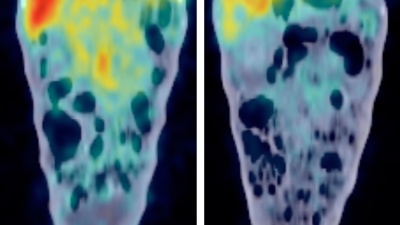

The four-year study completed by Georgia Tech is the first major national assessment of the health of those who live in major cities, the impact of rising temperatures and what city leaders can do to alleviate the crisis.